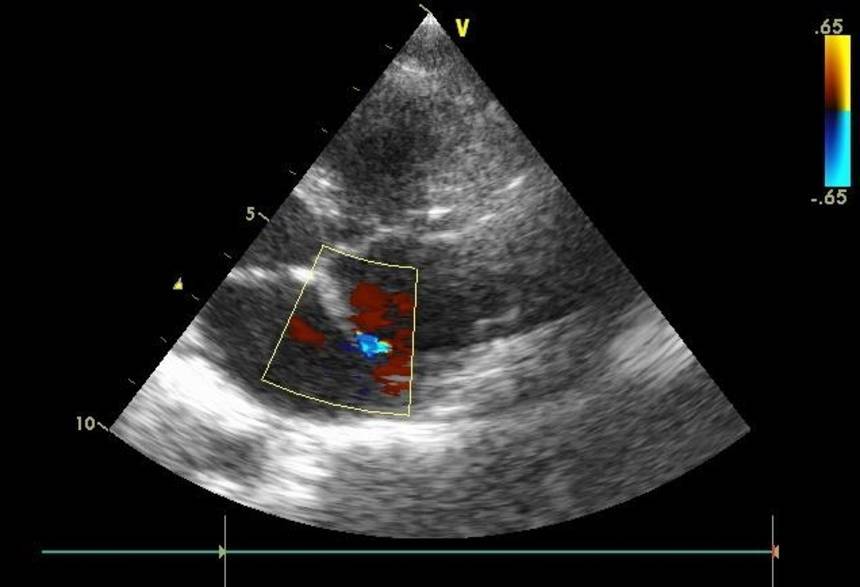

Основным способом выявления патологии у ребенка является УЗИ сердца. Альтернативное название манипуляции – ЭХО-кардиография. Данная процедура абсолютно безболезненна и безопасна, поэтому является методикой выбора при диагностике многих врожденных патологий сердца. Для того чтобы увеличить информативность исследования, необходимо использовать современные аппараты УЗИ, а прием должны вести опытные специалисты, которые способны заметить даже небольшие нарушения гемодинамики. Такой подход позволяет обеспечить достоверную диагностику патологий даже у самых маленьких пациентов.

Врожденные пороки сердца диагностирует неонатолог (порок сердца у новорожденных), семейный врач, педиатр (порок сердца у детей), терапевт (врожденный порок сердца у взрослых), детский кардиолог, кардиолог, специалист по ультразвуковой диагностике, эндоваскулярный хирург, кардиохирург. Самый доступный, безопасный и при этом очень информативный инструментальный метод диагностики – ЭхоКГ с допплерографией. Для диагностики сложных врожденных пороков сердца применяют рентген контрастное исследование (вентрикулографию, ангиографию), КТ и МРТ, в том числе с контрастированием.

Врожденный порок сердца диагностируют не только после рождения, но и внутриутробно с помощью ЭхоКГ с допплерографией

Это важно при сложных и несовместимых с жизнью дефектах. В первом случае беременность и роды ведут с учетом наличия порока; планируют кардиохирургическое вмешательство в первые дни и месяцы жизни. При несовместимых с жизнью пороках предлагают искусственное прерывание беременности